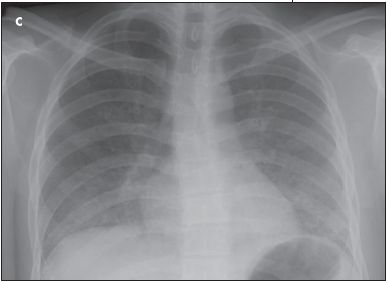

Coarse crackles were heard throughout the upper and lower lung fields bilaterally, and breath sounds were decreased. The abdomen was soft and nontender without hepatosplenomegaly. Compared with previous imaging studies, lateral (B) and posteroanterior (C) chest radiographs showed worsening pulmonary edema and bibasilar pulmonary opacities with air bronchograms. A CT scan confirmed the presence of severe bilateral pneumonia.